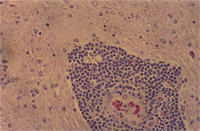

肉眼病變: 局部性慢性炎症見於整個腦組織,主要侵犯血管周圍形成很厚的非化膿性炎症細胞增生(圖1),包括淋巴球、組織球、類上皮細胞、吞噬細胞與少許漿細胞,偶爾亦有嗜中性球(圖2)。炎症細胞圍繞血管厚薄不一,圍繞不均勻,有時較集中於血管一端而呈偏心。又各種炎症細胞出現增生程度不均,有的圍繞為清一色淋巴球(圖3),有的則大部分為組織球或吞噬細胞(圖4)。特殊染色如PAS並無特殊發現,本病例又可看到一些血管變性(degenerated vessels)。病變發生於腦脊髓與腦膜,灰白質均可被侵犯,炎症細胞增生,侵犯非只限於血管周圍,亦可侵入腦實質neuropil。